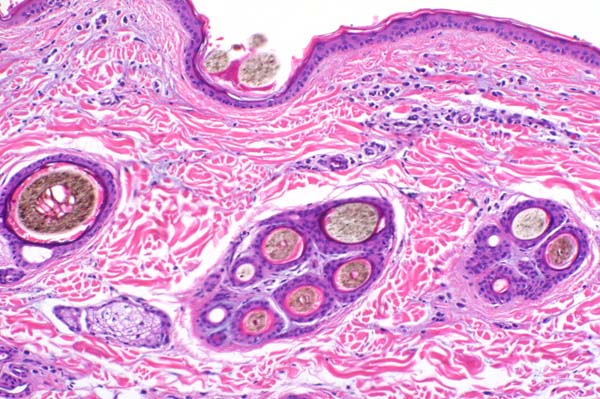

| 10x   |   Hematoxylin and Eosin | ||||

Collagen fibers are loosely arranged and separated by cellular infiltrates in the superficial dermis.